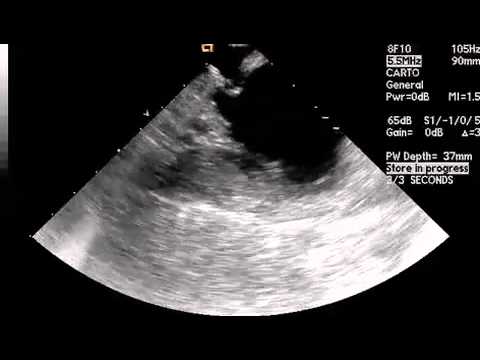

Video 9.1

Video 9.1 ICE video of left atrial anatomy in view of the mitral valve. At the apex of the ICE image sector, the right atrial chamber is seen. Below this appears the thin-walled fossa ovalis, below which is seen the left atrium. At 9 o'clock on the left atrium, the coronary sinus is seen in cross-section.